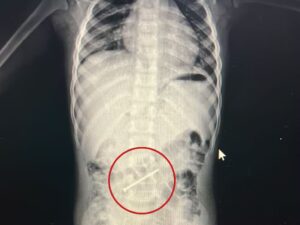

Um procedimento realizado na noite desta sexta-feira (16), no Hospital do Juruá, resultou na retirada de um prego que estava alojado no intestino de uma criança de 3 anos. A intervenção foi feita por meio de colonoscopia pelo médico Marlon Holanda, e o paciente apresentou boa recuperação.

O menino, identificado como Erick, mora com a família em Ipixuna, no Amazonas, e havia engolido o objeto cerca de seis dias antes de ser transferido para o Acre. Ao chegar à unidade hospitalar, a criança foi atendida pelo pediatra Rondney Brito e passou a ser acompanhada pelas equipes de endoscopia e cirurgia.

Durante todo o período de internação e no momento do procedimento, o paciente permaneceu estável, consciente e se alimentando normalmente. A retirada do prego ocorreu sem intercorrências, evitando a necessidade de uma cirurgia de maior porte.